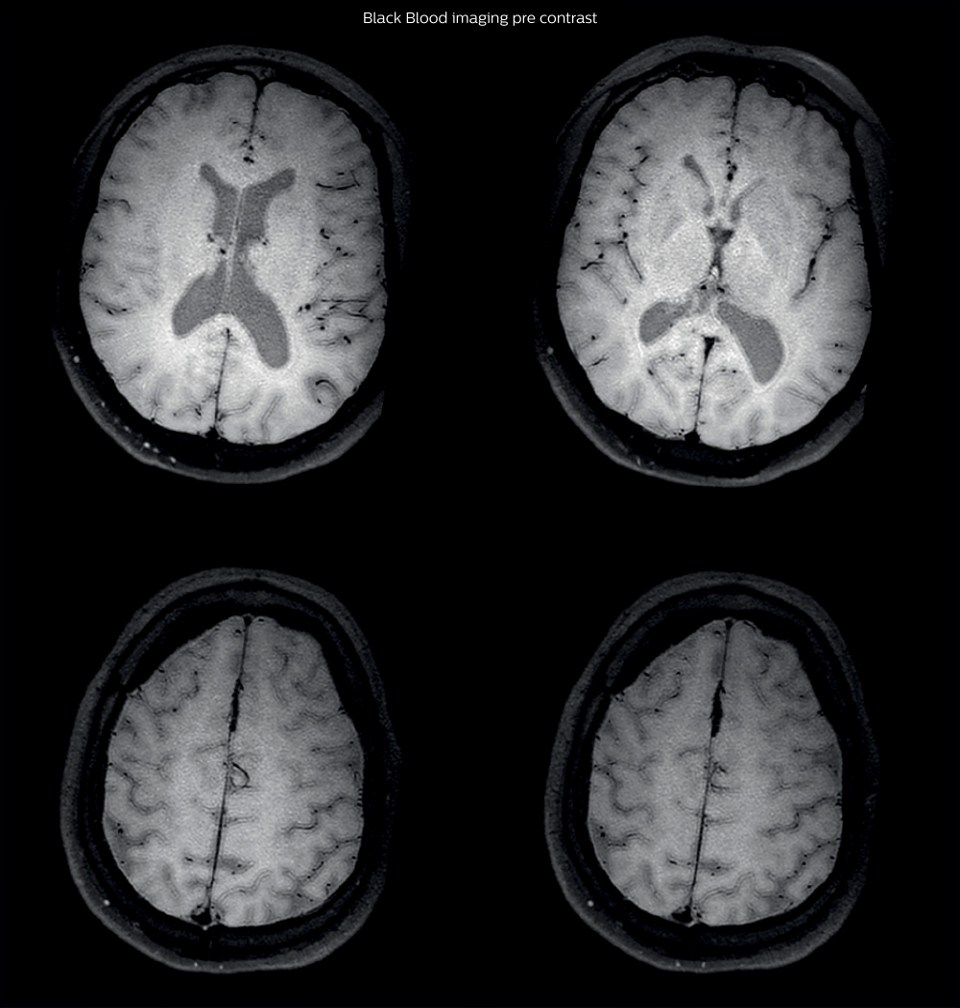

MRI examination with Black Blood imaging

After a conventional routine MR imaging examination, the suspicion of vasculitis arose, therefore we performed an MRI including Black Blood imaging in a separate session. The dedicated ExamCard includes diffusion, FLAIR, MR angiography

using TOF, and 3D T1 MRA with bolus injection. This ExamCard also includes Black Blood imaging before and after contrast. This examination was performed on our Ingenia 3.0T. Black Blood scan time 4:39 min, acquired voxel size 0.75 x 0.75 x 1.0 mm, 21 slices.

On FLAIR images we can see some nonspecific high signal abnormalities in frontal white matter bilaterally. On DWI we can see acute ischemic lesions which appear with high signal intensity. Arrows show vessel wall enhancement which appears concentric and homogeneous in different cerebral territories.

Black Blood Imaging Case 1 A2

Black Blood Imaging Case 1 B Pre contrast1